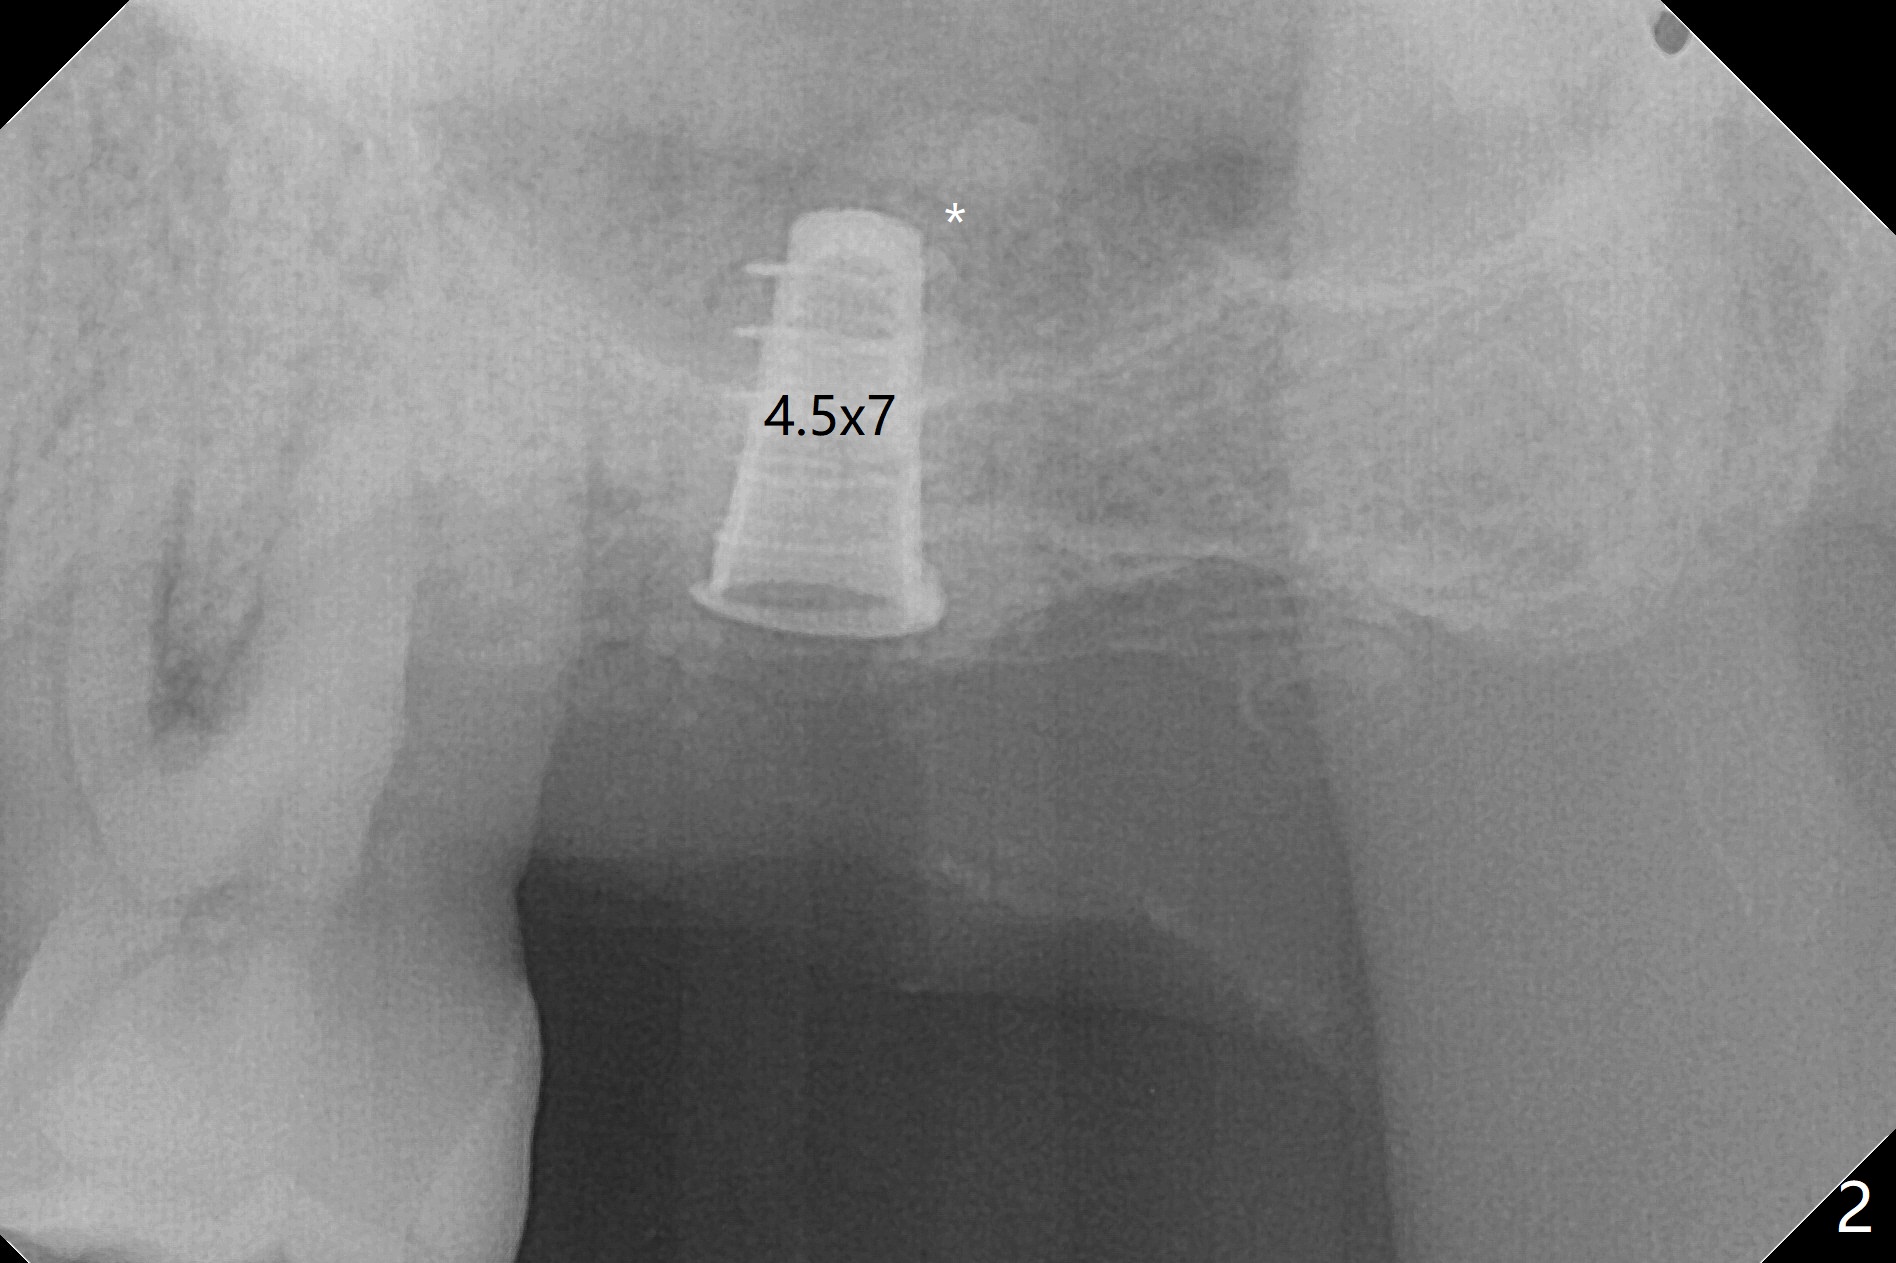

cartridge),植入短小植体(4.5x7毫米,原定(5x8.5毫米)图二),由于稳定性好,使用5.5毫米profile钻头后,放置5.5x4毫米愈合基台(图三)。术后病人没有什么上颌窦不适和分泌物。估计Novo

Bone在上颌窦里凝固了。其实左侧上颌窦粘膜术前增厚(图四,五:L),人工骨仿佛弥撒在上颌窦膜中(图六)。术后一周病人没有任何鼻窦症状。术后4.5月旋转愈合基台时,病人感到疼痛,终止取模(图七),两个月后复诊,做progressive loading。术后5.5月旋转愈合基台时,植体一起出来,但是上颌窦膜没有破,放置大一号植体(报废)扭力不够(图八),再大一号扭力可以(图九),放置愈合帽。由于邻牙长(图九:双箭头),牙周敷料逗留三周不掉(图十:P)。撤除后,伤口愈合正常。The

implant is stable upon uncover 3.5 months postop (Fig.11).

一个月后安置修复基台,开始progressive loading,临时牙冠没有咬合。